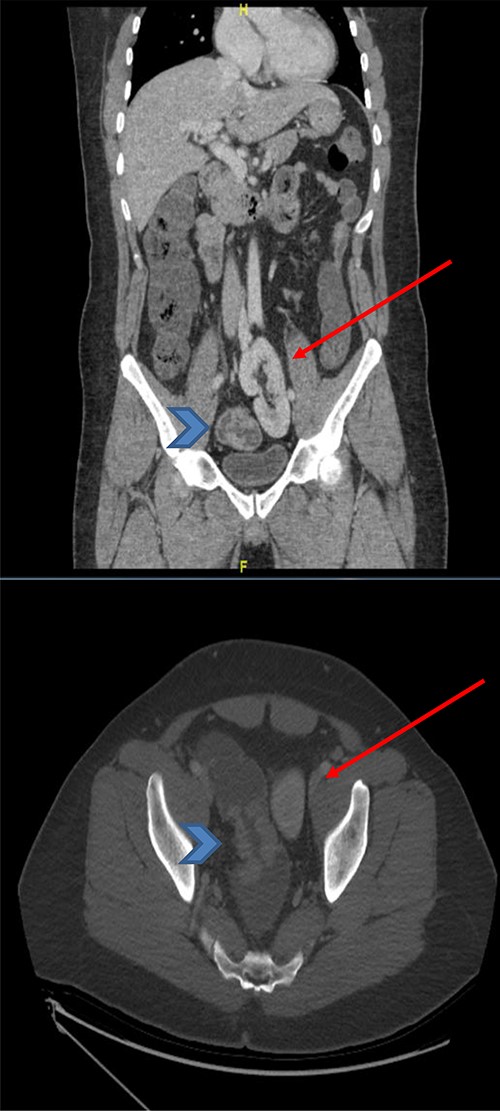

The basic lab Investigation showed Hgb level of 8.6 g/dL and CEA level of 4.8 ng/ml. On further investigation, colonoscopy revealed a large friable fungating circumferential rectal mass at 9 cm from anal verge extending to the distal sigmoid colon, it was nonobstructing with a length of 8 cm and the rest of the colon was normal. A biopsy from the mass was taken and showed invasive moderately differentiated adenocarcinoma. On further routine of radiological staging, CT of the chest, abdomen and pelvis confirmed the upper rectal mass with ectopic malrotated left kidney located in the lower abdomen and upper pelvis, opposite to L5-S1 vertebral bodies (Figs 1 and 2). There was no peritoneal disease or distant metastasis. Moreover, MRI pelvis showed again an upper rectal mass with mesorectal fat invasion and multiple lymph nodes (T3N2) and confirmed an ectopic left kidney (Figs 3 and 4).

MRI pelvis (sagittal view) showed upper rectal mass with mesorectal fat involvement (arrowhead) and ectopic pelvic kidney (arrow).